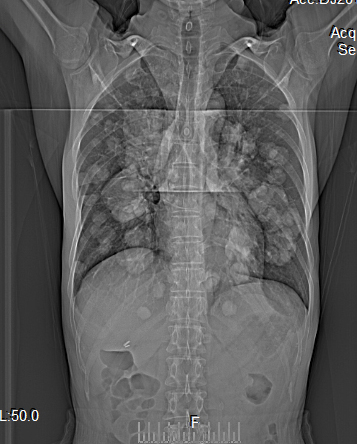

【病例】食管癌肺转移1例X线CT影像表现

性别:男,年龄:54岁,食管癌、胸痛、咳嗽

正确答案是:A、肺转移瘤;

[影像描述]

双肺多发转移灶,大小不等,呈棉花团样